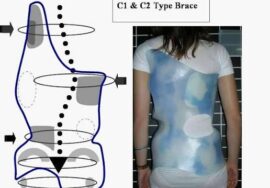

تأثير الحبل الشوكي الضيق على علاج اعوجاج العمود الفقري غير الجراحي

إذا كان الحبل الشوكي الضيق يحدد مدى التصحيح الجراحي، فهل يمكن أن يؤثر أيضًا على العلاجات غير الجراحية مثل التمارين والعلاج بالحزام؟ الإجابة نعم. كثير من مراكز علاج الاعوجاج تطور حاليًا برامج تهدف إلى زيادة مرونة الحبل الشوكي وتمديده تدريجيًا، ما يمنح التمارين والحزام فرصة أفضل لتحقيق نتائج ملحوظة.

تحسين مرونة الحبل الشوكي يشبه “إخماد النار” التي تسببها قوة الشد: كلما زادت مرونة الحبل، أصبح من الأسهل على الحزام والتمارين المساعدة في إعادة توازن العمود الفقري بدون المخاطرة بالشلل.

العلاج غير الجراحي: استخدام أحزمة طبية مخصصة وتمارين لتقوية العمود الفقري وزيادة مرونة الحبل الشوكي.